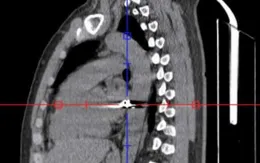

đạn bắn xuyên ngực